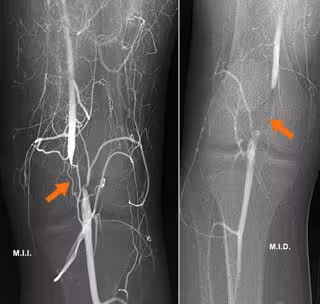

Atrapamiento de la arteria poplítea, una causa infrecuente de claudicación en personas jóvenes.

El diagnóstico precoz del Síndrome de Atrapamiento de la Arteria Poplítea (SAAP), detalla el responsable de la Unidad de Radiología Vascular Intervencionista del Hospital Ruber Internacional, Santiago Zubicoa, se realiza en la consulta realizando un eco-doppler

dinámico de miembros inferiores. Posteriormente, el diagnóstico se confirmará con una arteriografía dinámica también de ambas extremidades inferiores. "Una vez realizadas las pruebas de imagen que nos confirmen el diagnóstico de SAAP debemos programar el tratamiento quirúrgico", ha matizado.